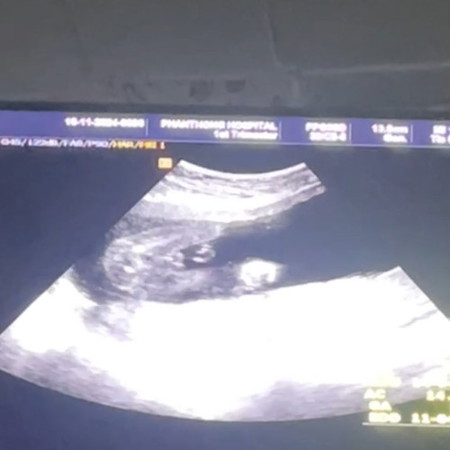

ดูเพศว่าผู้หญิงหรือผู้ชายค่ะ

ผู้ชาย หรือ ผู้หญิง คะ ช่วยดูหน่อยค่ะแม่ๆ ดูยังไงคะ

เราว่าชายค่ะ

ชายแน่เลย

เหมือนจะชาย

ชาย